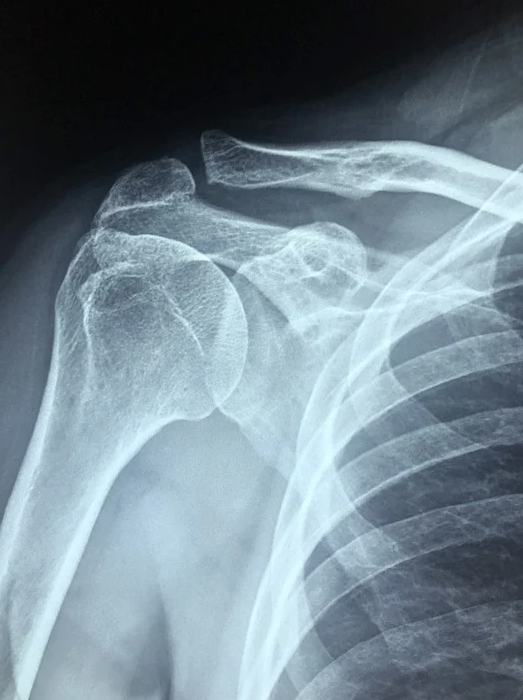

오십견 증상 및 단계 알아보기

오십견은 4~50대 많이 발생하는 어깨 질환입니다.

특히 어깨나 팔에 통증이 심하여 팔을 쉽게 올릴 수 없고 심지어 옷을 입기도 불편한 경우도 생기는 증상입니다.

원인은 어깨관절의 활동범위가 넓기 때문에 뼈나 이외 근육등 조직 간에 서로 당기는 것 때문이기도 하며 여러 가지 요인이 겹쳐 우리가 흔히 말하는 오십견으로 나타나게 됩니다.

오십견의 원인은 특별한 외상이 없어도 어깨 관절을 둘러싸고 있는 조직 간의 염증에 의해 유착이 생기며 발생하는데요.